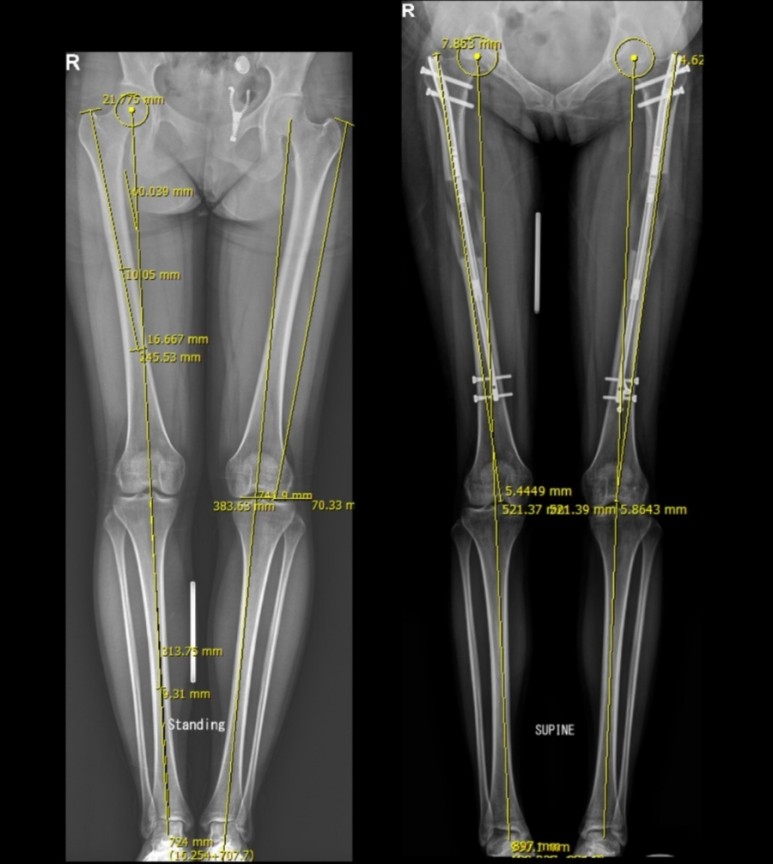

3등은 종아리 속성연장입니다. 종아리 속성연장은 여러 면에서 가장 많이 시행되는 보편적이고도 가장 이변이 없는 안정적인 수술이지만, 핀 통증은 키 연장 후반부에 환자들을 괴롭힙니다. 이때가 재활치료가 가장 필요한 시기지만, 재활 치료를 못하게 괴롭히는 방해자도 이 핀 통증입니다. 재활치료를 줄이면 연장은 더 할 수 있지만, 정확한 정렬 사진 측정이 불가능해지므로 재활이 부족한 종아리 속성연장 환자들은 정확한 정렬사진을 찍기 불가능하고, 2차 수술인 외고정 제거수술을 하고 난후 교정수술을 해야 하는 경우가 종종 있습니다. 고연장은 하고 싶고, 재활은 못하겠다는 상황이 많은 재활을 힘들어 하는 종아리 속성연장 환자에게서 나타나는 현상입니다. 외고정을 제거 후에 교정을 다시 하는 수술실 교정은 비교적 간단하지만, 가능한 2차 수술 외고정 제거 수술 전에 재활을 충분히 한 후 정렬교정을 마치는 것이 유리합니다.